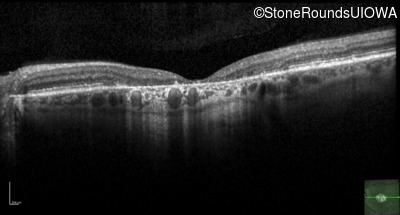

Age at visit: 52 years

This 52 year old man first noticed reduced visual acuity at age 21.

Age at visit: 54 years

Age at visit: 59 years